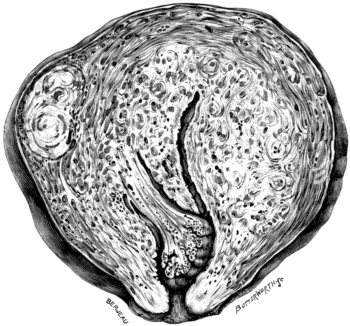

| 110. | The Normal Angle of the Anterior Chamber | 217 |

| 111. | The Angle of the Anterior Chamber from a Case of Recent Glaucoma | 218 |

| 112. | The Angle of the Chamber in a Case of Chronic Glaucoma | 219 |